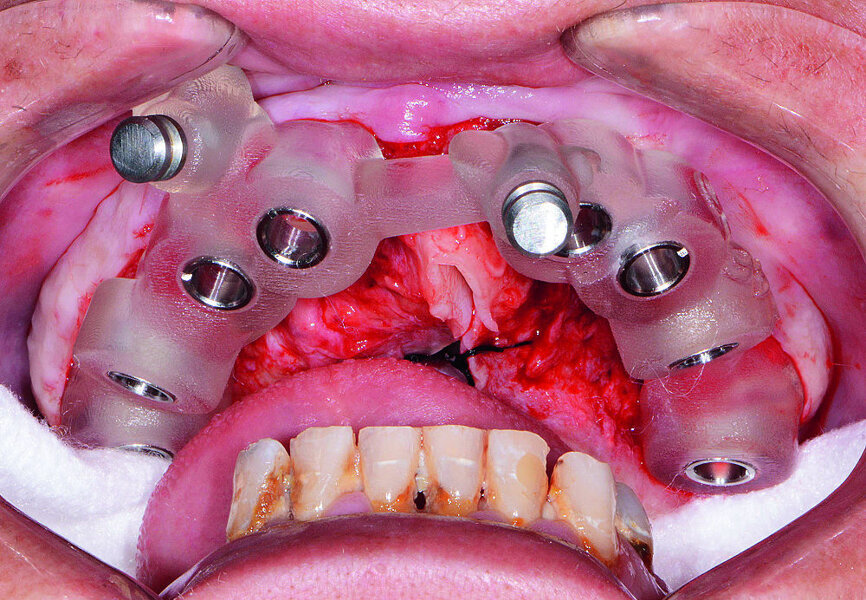

Quatre mois plus tard (Figs. 17 et 18), les piliers de cicatrisation de l’arcade maxillaire ont été désenfouis par une technique chirurgicale, puis les tissus ont été soigneusement refermés. Après la cicatrisation, soit environ deux à trois semaines plus tard, des coiffes d’empreinte ont été mises en place sur les implants coniques Hahn et des empreintes ont été prises au moyen d’un porte-empreintes fermé et d’un matériau en polysiloxane de vinyle (Panasil, de Kettenbach). Un enregistrement de l’occlusion a également été réalisé (Futar, de Kettenbach). Les prothèses immédiates étant bien adaptées et satisfaisantes selon l’avis de la patiente, des répliques ont été envoyées au laboratoire aux fins de concevoir les restaurations définitives. Le laboratoire a utilisé les empreintes pour couler et scanner des modèles en plâtre-pierre, créer une image numérique des arcades de la patiente sur lesquelles les modèles des piliers personnalisés, et des restaurations à sceller ont été conçus. Les piliers personnalisés en titane Inclusive ont été fabriqués avec les composants du sourire en polyméthacrylate de méthyle (PMMA) correspondants.

La patiente est revenue pour une évaluation clinique du modèle prothétique. Les piliers personnalisés ont été mis en place à l’aide de guides de positionnement en acrylique, fournis par le laboratoire pour faciliter l’orientation adéquate pendant l’insertion (Fig. 19). Grâce à la précision de la technique de conception numérique, l’ajustage des piliers personnalisés s’est révélé parfait et définissait des limites marginales positionnées exactement, ou à une distance négligeable de la surface gingivale. Cette précision a fortement simplifié l’élimination de l’excès de ciment des limites marginales et illustre les avantages des piliers produits en CFAO.